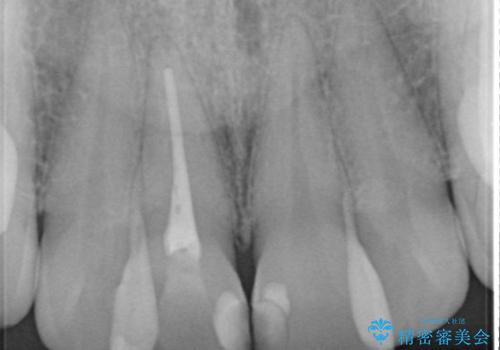

- 前歯の色が変色してきたことを主訴に来院されました。

根管治療から被せものまで治療を行いました。